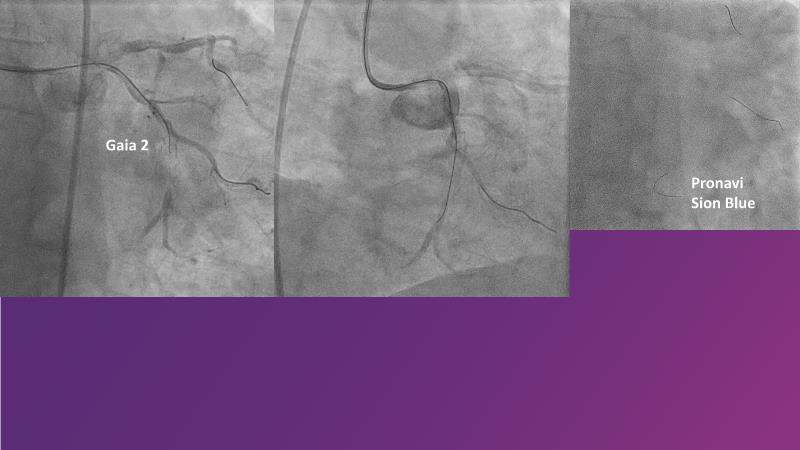

Don't miss this session for expert guidance on preparing and managing complex lesions. Gain insights into choosing the right tools, including microcatheters and balloons, for optimal treatment outcomes. Explore the innovative features of flagship devices for complex PCI, and Pronavi microcatheter and Alveo HP CTO balloon to treat complex CTO lesions. Learn about the safety and efficacy of the Wedge NC scoring balloon, the importance of using POT dedicated balloons in POT and DOT techniques, and get updated tips and tricks from ongoing clinical practices.

- To gain insights on Pronavi microcatheter and Alveo HP CTO balloon to treat complex CTO lesions, understand the safety and efficacy of lesion preparation with Wedge NC scoring balloon and the significance of using POT dedicated balloon in POT and DOT technique